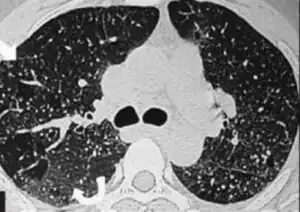

Pulmonary siderosis causes changes within the lungs that are clearly visible in tissue samples, x-ray images and other radiological studies.[2] In a tissue sample from alveoli patchy deposits of iron can be seen throughout the sample.[4]